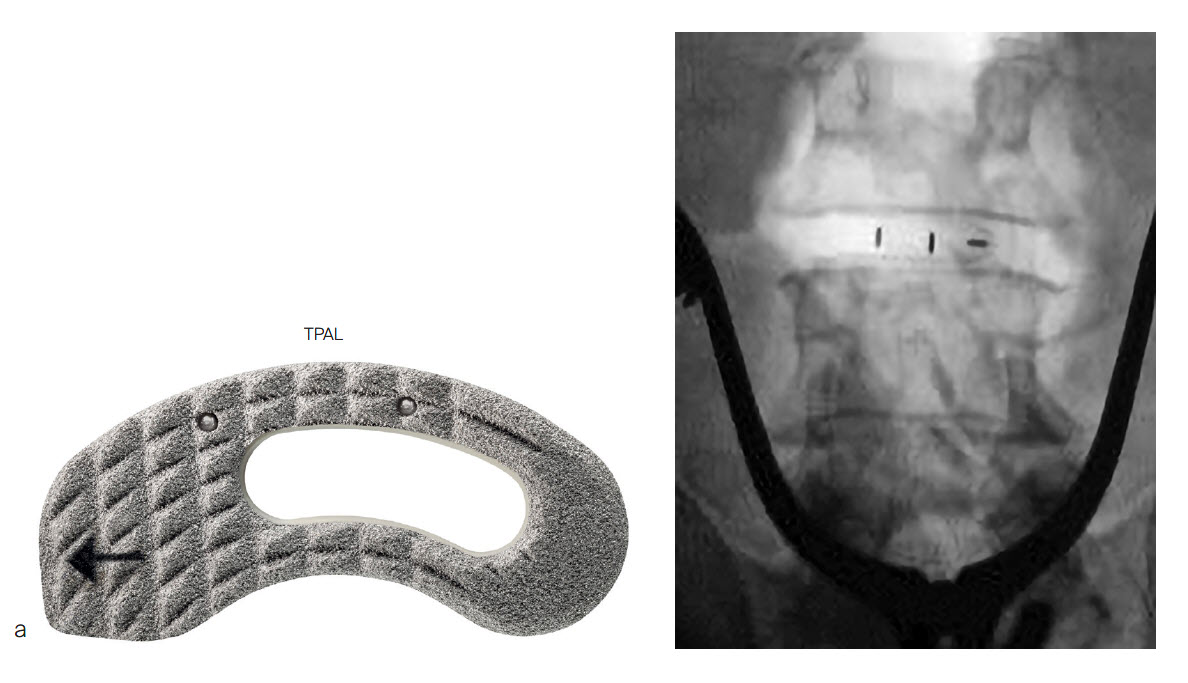

PROTI 360° is a family of integrated titanium interbody cages (Fig 1) that promote spinal fusion, intended for use in patients with degenerative disc disease (DDD). The cage family includes the ACIS PROTI 360° System for cervical fusion, and the T-PAL PROTI 360° System and CONCORDE PROTI 360° Systems for lumbar interbody fusion.

The PEEK core of the PROTI 360° cage has favorable imaging characteristics which support the postoperative assessment of fusion, while the titanium outer layer allows measurement of cage positioning. Clinically, depending on the image quality, plane of view, and patient anatomy, the PROTI 360° cage may show a ghost image of the entire cage on fluoroscopic images (Fig 7). CT images show minimal scatter around the implant (Fig 8).

The PROTI 360 cages are available as sterile implants and are compatible with ACIS System (Fig 9a), T-PAL Interbody System (Fig 9c) and CONCORDE Bullet (Fig 9c) instrument sets. The ACIS implants are available in 5-10mm heights, in Lordotic Small, Standard, and Large designs and in Parallel Standard or Convex Standard. The CONCORDE implants are available in Parallel and Lordotic designs (7-15 mm heights, 23 and 27 mm lengths). The T-PAL implants are available in the High Curve design (7-15 mm heights, 10 x 28, 12 x 32 footprints).